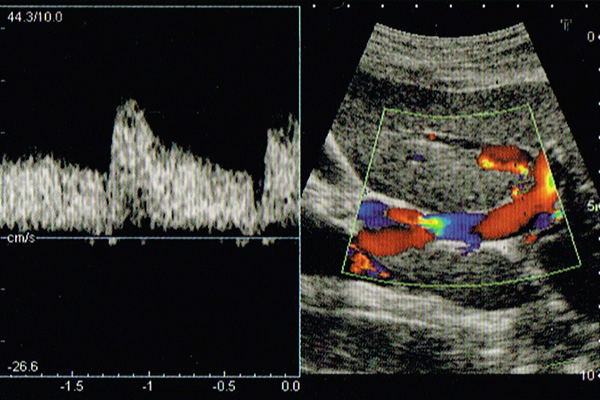

超音波による検査、いわゆる「腹部エコー」です。

対象は、肝臓、胆のう、腎臓、すい臓などの腹部の臓器全般です。なかでも胆石、早期肝臓がんの発見に有用です。

フルデジタル超音波診断装置TOSHIBA Nemio17を使用しています。